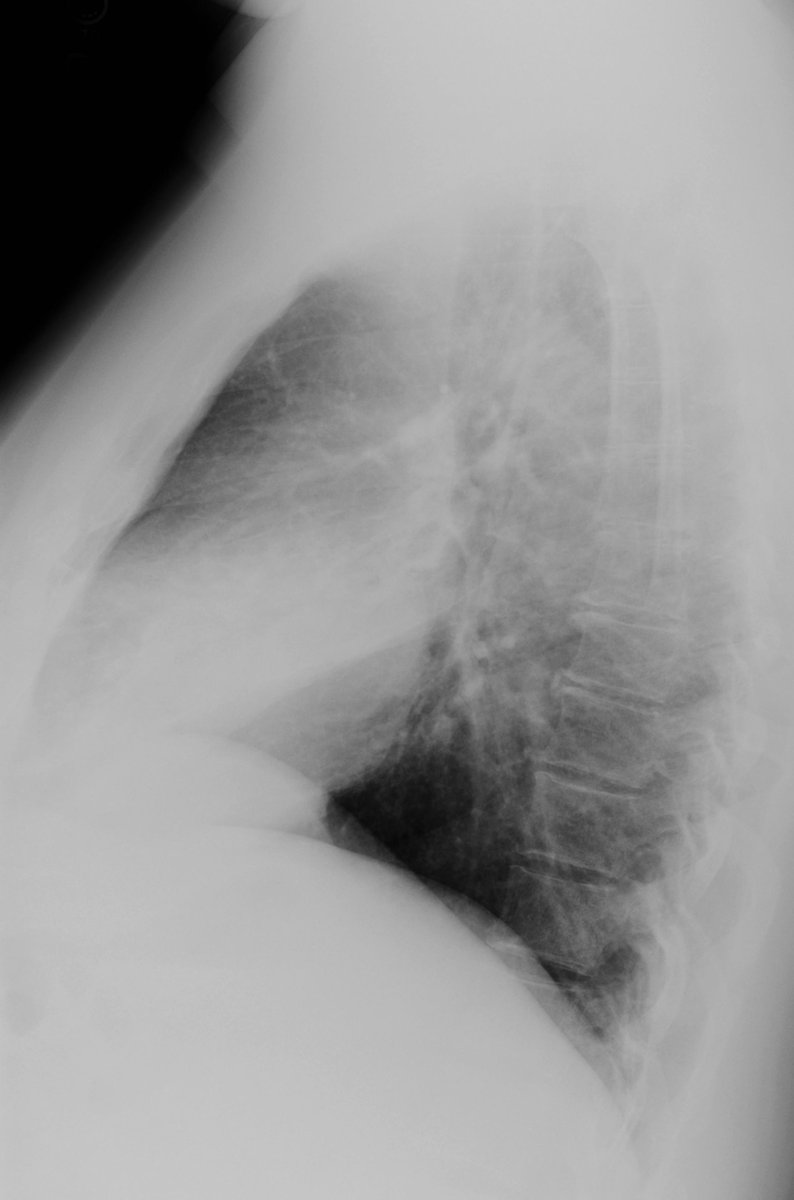

Sign? A. Hilum overlay B. Silhouette C. Air bronchogram D. Scimitar

#ChestRadEdu#meded@TanMohammedMD@DarelHeitkamp Answer: Silhouette (RML pneumonia). PA - opacity obscuring R heart border. Lateral - opacity overlying heart, marginated inferiorly by major fissurepic.twitter.com/KYSpuxPmdk